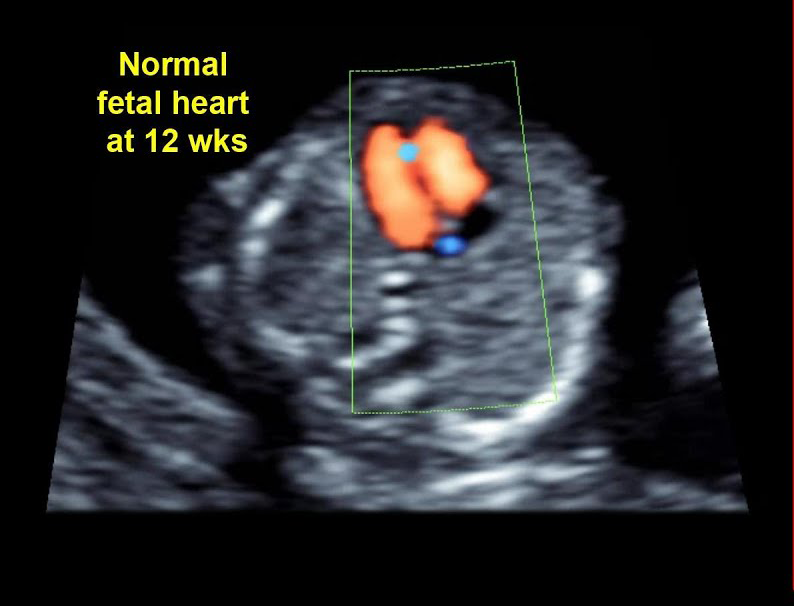

اکوکاردیوگرام جنین را می توان با اطمینان در هر زمانی پس از هفته 17-18 بارداری انجام داد. با این حال، فناوری جدیدتر از جمله مبدل‌های اندوواژینال می‌تواند تصاویری از قلب را تا 12 هفته به دست آورد. اگر اسکن قبل از هفته 18 انجام شود، احتمالاً از شما خواسته می‌شود که برای دریافت تصاویر قطعی‌تر مراجعه کنید تا یافته‌های مطالعه اولیه را تأیید کنید. در برخی موارد 18 هفته هنوز خیلی زود است.

اکوکاردیوگرام جنین را می توان با اطمینان در هر زمانی پس از هفته 17-18 بارداری انجام داد. با این حال، فناوری جدیدتر از جمله مبدل‌های اندوواژینال می‌تواند تصاویری از قلب را در 12 هفته به دست آورد. اگر اسکن قبل از 18 هفته انجام شود، احتمالاً از شما خواسته می‌شود که برای دریافت تصاویر قطعی‌تر مراجعه کنید تا یافته‌های مطالعه اولیه را تأیید کنید. در برخی موارد 18 هفته هنوز خیلی زود است.

یک تصویر دو بعدی (مطالعه 2 بعدی و 3 بعدی) از قلب جنین می سازد که همانطور که در ویدیوی بالا سمت چپ مشاهده می شود، روی صفحه نمایش داده می شود و قلب طبیعی جنین را با 4 حفره نشان می دهد.

جریان خون قلب جنین را مطالعه می کند (مطالعه داپلر طیفی و داپلر رنگی) همانطور که در ویدیوی سمت چپ بالا مشاهده می شود که قوس آئورت را با جریان خون (رنگ قرمز) نشان می دهد.